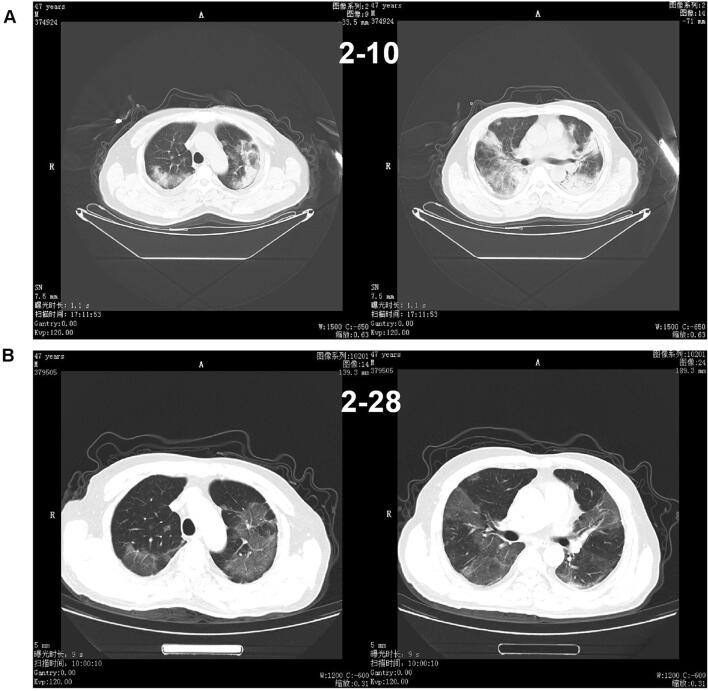

Among the 194 patients, 141 (72.68%) showed abnormal chest CT images, consisting of 101 cases (52.06%) of bilateral pneumonia and 40 cases (20.62%) of unilateral pneumonia (Table 1). Some lesions might have a mixed pattern of consolidation in the center and ground glass opacity in the periphery (Fig. 1). In severe or critically severe patients, multiple patches or an integrated larger patch of ground glass opacity, consolidation or mixed consolidation and ground glass opacity might present in bilateral lungs (Fig. 2).

Fig. 2.

Chest CT of a male patient, 47 years old. a He underwent a chest CT examination on February 10, which showed multiple lesions of peripheral ground glass opacity with consolidation and fibrosis in the two lungs. b 18 days after treatment, the CT images of February 10 showed a decrease in density of the pulmonary lesions with fibrosis format